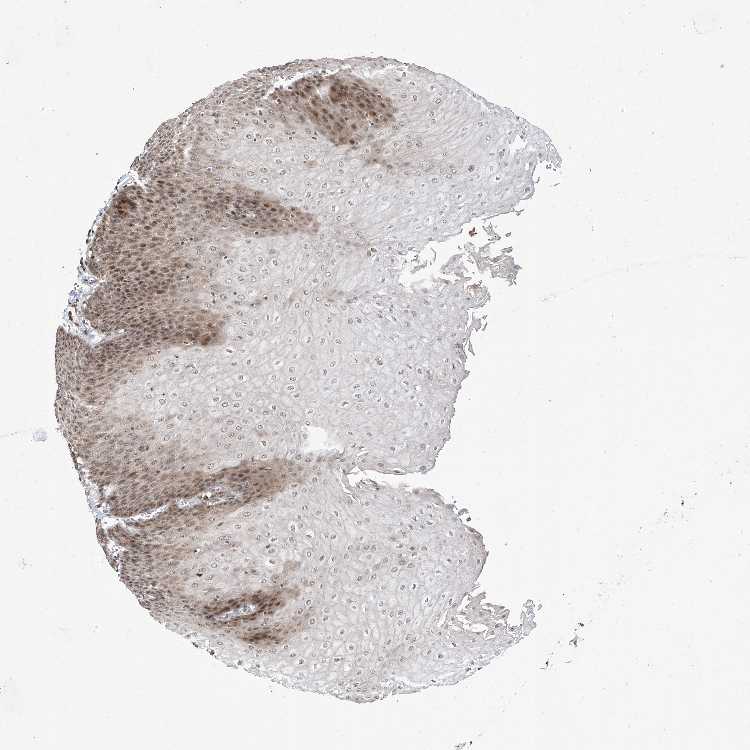

ESOPHAGUS - Antibody stainingi

Antibody staining in the annotated cell types in the current human tissue is reported as not detected, low, medium, or high, based on conventional immunohistochemistry profiling in selected tissues. This score is based on the combination of the staining intensity and fraction of stained cells.

Each image is clickable and will lead to virtual microscopy that enables deeper exploration of all samples and also displays staining intensity scores, fraction scores and subcellular localization as well as patient and tissue information for each sample.

Antibody HPA030267

Squamous epithelial cells Medium